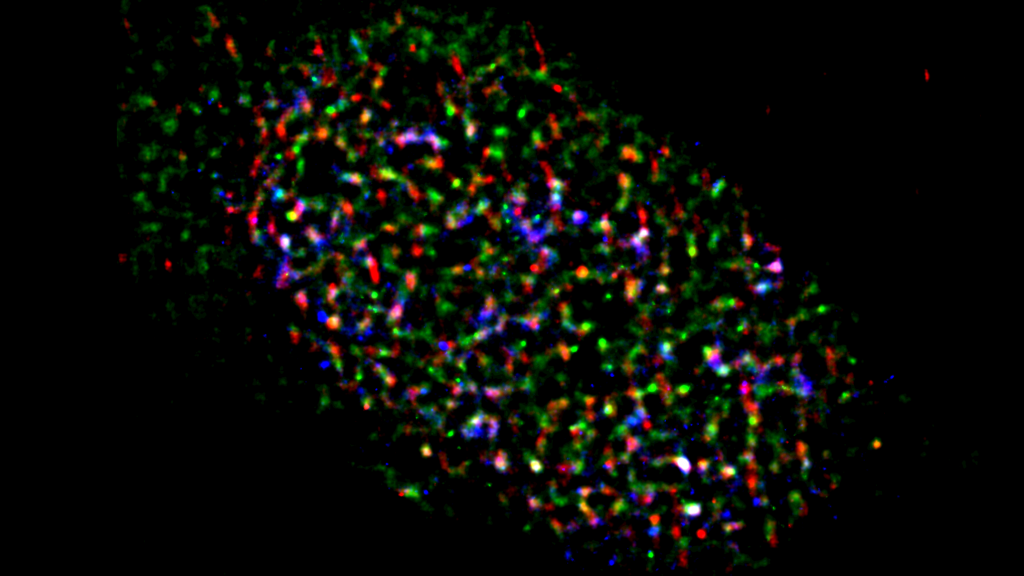

In a new study, led by Yutaka Kondo and Miho Suzuki at Nagoya University Graduate School of Medicine, the investigators identified the role of the lncRNA TUG1. They found that TUG1 suppresses the potentially harmful R-loops together with two proteins, DHX9 and RPA32. Taken together, the TUG1-RPA-DHX9 interaction is an indispensable mechanism for regulating R-loops in regions that are known to be susceptible to DNA damage and mutations. Their findings were published in Nature Communications.